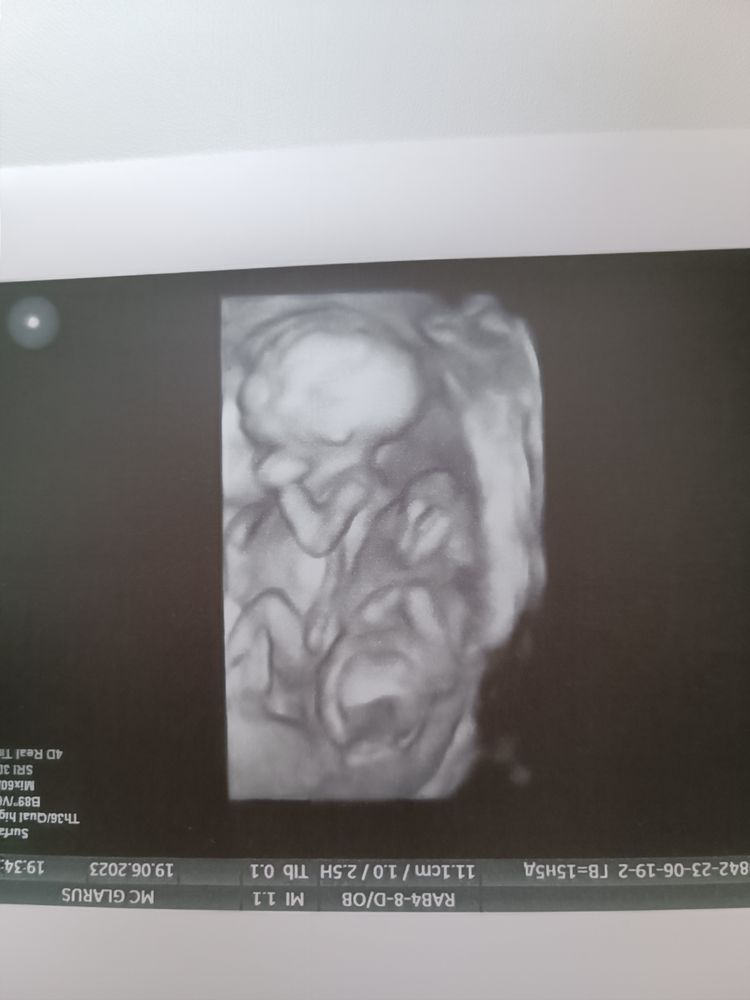

33 недели узи ди ди двойни, разница в весе💙💙 Скрининг у Костюкова К.В. в Кулакова.

Двойня, узнали пол💕